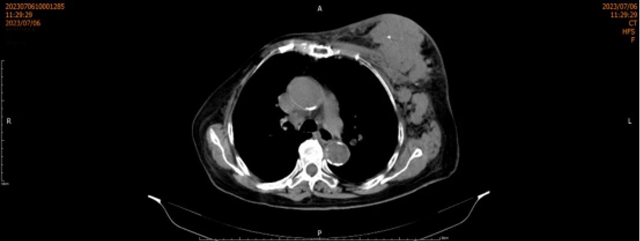

近日,家住天兴镇的72岁邓大爷因“反复中上腹部疼痛2+年,加重1周”到福欣医院就诊。门诊以“腹痛”收治入院,住院期间行电子胃镜提示:胃体新生物,并取活检,病检示:“胃体”活检标本,低分化癌,建设免疫組化协诊明确分型,诊断为“胃恶性肿瘤”。考...